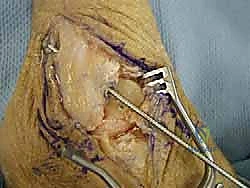

خطوات العملية الجراحية خطوة بخطوة مع الأستاذ الدكتور محمد هطيف

تتميز الجراحة في عيادة الدكتور هطيف بالدقة المتناهية واستخدام أحدث التقنيات العالمية. إليك كيف تتم العملية:

3. تجهيز الطعم (Graft Preparation):

يتم تحضير الطعم الليفي (Allograft) وتشكيله بدقة ليتناسب تماماً مع الحجم والطول المطلوبين لتعويض أربطة ATFL و CFL المفقودة.

6. الإغلاق والجبيرة:

يتم إغلاق الشقوق الجراحية الصغيرة بغرز تجميلية، ثم يوضع الكاحل في جبيرة أو حذاء طبي واقٍ لحماية الأربطة الجديدة أثناء بدء مرحلة الالتئام.